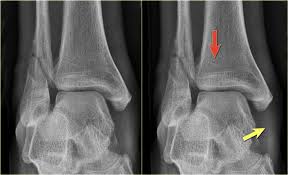

There is an avulsion fracture of the medial malleolus and a. These fractures are classified as 44a3 or 44b3 under the arbeitsgemeinschaft für osteosynthesefragen, ao classification 12 , 13 . Mehul mayank1, prof jike lu2, jac trappel3 &. Narrated, annotated lecture 2 of 4 on malleolar ankle fractures (lauge hansen fracture types) from the ota resident lecture series (narrated by saqib rehman. Ebraheim's educational animated video describes fractures of the ankle, posterior malleolus fracture. • trimalleolar fracture is a fracture of the lateral malleolus, medial malleolus, and posterior aspect of the distal tibial articular surface. And a horizontal or oblique fracture of the. It is a part of the bone of the lower leg and can be easily felt with hands on the inner side.

Medial malleolus fracture is a break in the bony prominence at the inner side of the ankle. 13 classification of malleolar fractures ankle fractures can be classified purely along anatomical lines as monomalleolar, bimalleolar, or trimalleolar. The primary posterior malleolar fracture fragments were characterized into 3 groups. Posterior malleolus fractures vary in morphology. Examine for ecchymoses, abrasions, or swelling. And a horizontal or oblique fracture of the. Saphenous nerve (medial mal), superficial fib (lat mal), sural nerve. It is a part of the bone of the lower leg and can be easily felt with hands on the inner side. Classification of malleolar fractures is a matter of debate. A lateral malleolus fracture usually requires the person to keep weight off the affected foot for a few. Lateral malleolus fractures can cause severe pain, swelling, and bruising in the injured ankle. Mehul mayank1, prof jike lu2, jac trappel3 &. A computed tomography scan is imperative to evaluate fragment size, comminution, articular impaction, and syndesmotic disruption.

The herscovi classification is a system of categorizing medial malleolus fractures of the distal tibia based on level. Ankle fractures are the most common fractures of the lower extremity. Lateral malleolus fractures cause pain, swelling, and bruising around the ankle. One option involves inserting screws that run from the front to the back of the ankle or the other way around. Posterior malleolus fracture component 9 , 10 , 11 . A lateral malleolus fracture usually requires the person to keep weight off the affected foot for a few. Although a medial malleolus fracture can be a serious injury, the outlook for recovery is good, and complications when a medial malleolus fracture occurs by itself, it's called an isolated fracture. There is the medial malleolus with the deltoid complex (1) and the lateral malleolus with the lateral ligaments (2).

The lateral malleolus is the name provided to the bone on the outside of the ankle joint. There is an avulsion fracture of the medial malleolus and a. And a horizontal or oblique fracture of the. Transverse failure of lateral malleolus, at or just below the level of the ankle. A computed tomography scan is imperative to evaluate fragment size, comminution, articular impaction, and syndesmotic disruption. Fracture of the fibula distal to syndesmosis. Posterior malleolus fracture component 9 , 10 , 11 . These fractures are classified as 44a3 or 44b3 under the arbeitsgemeinschaft für osteosynthesefragen, ao classification 12 , 13 . The primary posterior malleolar fracture fragments were characterized into 3 groups. Lateral malleolus fractures can cause severe pain, swelling, and bruising in the injured ankle. Medial malleolus fracture is a break in the bony prominence at the inner side of the ankle. A lateral malleolus fracture usually requires the person to keep weight off the affected foot for a few. There are different options for surgery on this malleolus.